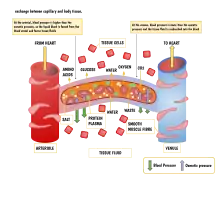

The capillary wall performs an important function by allowing nutrients and waste substances to pass across it. Molecules larger than 3 nm such as albumin and other large proteins pass through transcellular transport carried inside vesicles, a process which requires them to go through the cells that form the wall. Molecules smaller than 3 nm such as water and gases cross the capillary wall through the space between cells in a process known as paracellular transport.[19] These transport mechanisms allow bidirectional exchange of substances depending on osmotic gradients.[20] Capillaries that form part of the blood–brain barrier only allow for transcellular transport as tight junctions between endothelial cells seal the paracellular space.[21]

Starling equation

The transport mechanisms can be further quantified by the Starling equation.[20] The Starling equation defines the forces across a semipermeable membrane and allows calculation of the net flux:

where:

- is the net driving force,

- is the proportionality constant, and

- is the net fluid movement between compartments.

By convention, outward force is defined as positive, and inward force is defined as negative. The solution to the equation is known as the net filtration or net fluid movement (Jv). If positive, fluid will tend to leave the capillary (filtration). If negative, fluid will tend to enter the capillary (absorption). This equation has a number of important physiologic implications, especially when pathologic processes grossly alter one or more of the variables.

According to Starling's equation, the movement of fluid depends on six variables:

- Capillary hydrostatic pressure (Pc)

- Interstitial hydrostatic pressure (Pi)

- Capillary oncotic pressure (πc)

- Interstitial oncotic pressure (πi)

- Filtration coefficient (Kf)

- Reflection coefficient (σ)